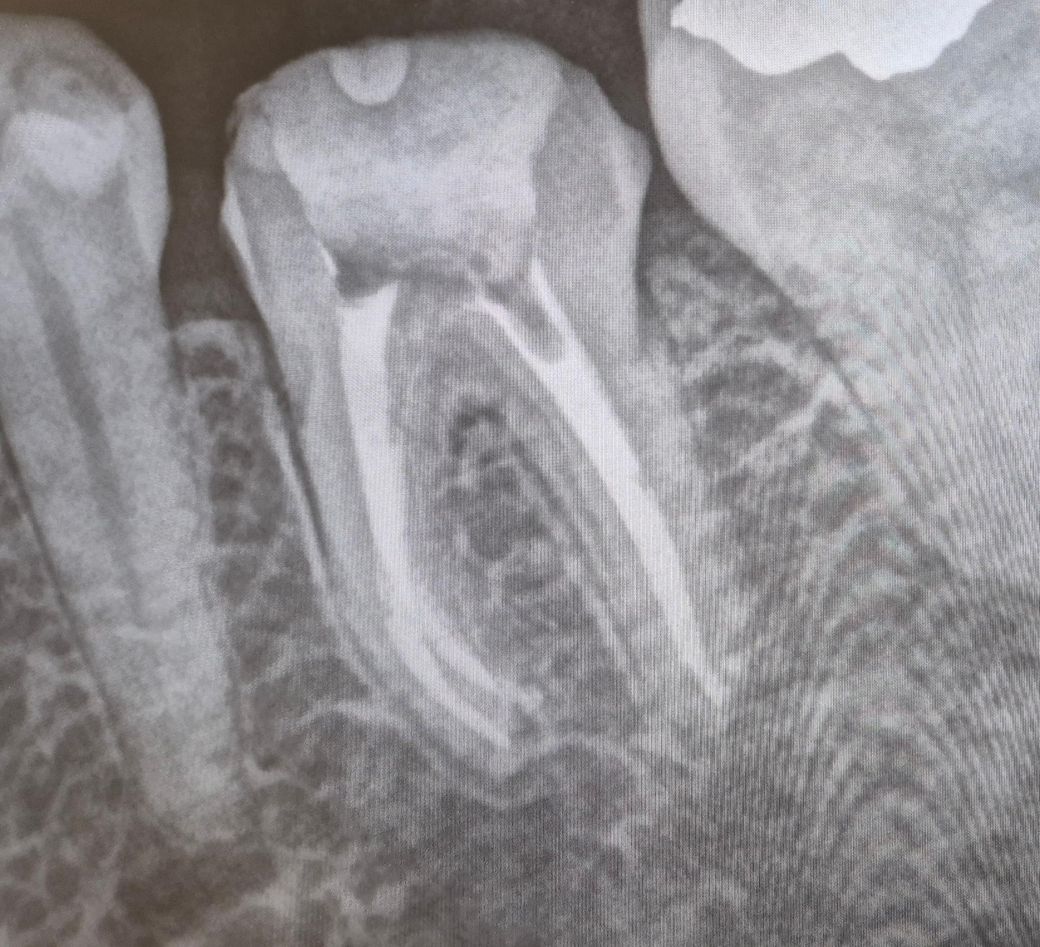

엑스레이 보고 어떻게할지 솔루션 부탁드립니다

7일전 신경치료 완료

아래 엑스레이 완료후 사진

근관에 충전재 아래와 같이 보충됨

더불어 근관내 충전 상태 불량 같은데

사진으로 봤을 경우에는 근관 내는 매우 충전이 잘 된 것으로 보입니다. 중간에 메꿔져 있지 않는 부분은 크게 문제가 되는 부분이 그건 아닙니다.

신경치료를 꼼꼼하게 했음에도 불구하고 지속적으로 통증이 있다면 뿌리의 금이 갔을 가능성이 높습니다. 뿌리에 금이 갔을 경우에는 치아를 발치하는 방법이 치료 방법이 될 수 있습니다.

엑스레이 상으로는 신경치료가 잘된거 같습니다. 증상이 잇다면 일단 임시치아로 먼저 사용해보시는게 좋을것같습니다.

1. 신경치료 자체는 훌륭하게 잘 된 것 같습니다

2. 미세하게 크랙이 있어서 그럴 수도 있고요, 지금 상태에서는 조금 더 지켜보거나 임시치아를 만들어 치아를 보호해주고 기다려보는 방법 밖에 없습니다.